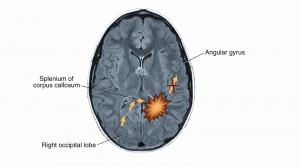

Alexia without agraphia is most often acquired secondary to occlusion of the left posterior cerebral artery without involving the angular gyrus.[1][4][5][7] In most right-handed people the dominant hemisphere is on the left side.[1][4][7] Knecht et al demonstrated an association between handedness and the language dominant hemisphere.[12] Knecht found that the incidence of right hemisphere language dominance increased linearly with the degree of left handedness.[12] Four percent of strong right handers, 15% of ambidextrous individuals, and 27% of strong left handers had right hemisphere language dominance.[12] This affects the input from the left visual cortex to the angular gyrus, which often leads to a right homonymous hemianopia.[5] However, there are cases that may not exhibit a complete right homonymous hemianopia but instead exhibit right hemiachromatopsia or color anomia.[3] In the latter, the lesion was located at the mesial occipitotemporal region in the left hemisphere.[3] In addition, infarction of the splenium (the posterior part of the corpus callosum) affects fiber tracts from the right visual cortex to the left angular gyrus but does not affect the right visual cortex.[1][4][5] Critical lesions have been identified to be at or around the visual word form area (VWFA).[13] Speech, writing, and vision in the right visual cortex are spared.[5] However, the patient is not able to read since visual information is not transmitted to the language area.[5] If the structures anterior to the splenium are not intact, the patient will also present with agraphia. Additionally, if the lesion is at the left angular gyrus, other symptoms could be present such as finger agnosia, acalculia and right left confusion, a syndrome called Gerstmann syndrome.[14] Recently, a new classification has been proposed for pure alexia stratifying based on neuroanatomical location. Lopez et al suggests referencing posterior lesions involving the splenium of the corpus callosum or the paraventricular white matter as disconnection alexia and naming more anterior lesions in the occipito-temporal cortex with damage of the visual word form area as cortical alexia. Disconnection alexia typically presents with visual deficits whereas cortical alexia can be thought of as pure alexia.[1]

A CT scan and/or MRI of the brain with and without gadolinium can help to identify and differentiate a stroke from other etiologies such as abscess, tumors etc. MRI typically reveals a lesion of the left occipital lobe with an extension into the splenium of the corpus callosum, corresponding to the vascular distribution of the posterior cerebral artery.[5][7] An EEG may demonstrate slowing or epileptiform discharges over the left posterior temporal and occipital regions indicating a structural disturbance.[5] (See the image to observe the affected areas) Patients with PCA stroke should undergo the usual and customary evaluation and management of stroke risk factors including thrombotic and embolic etiologies.